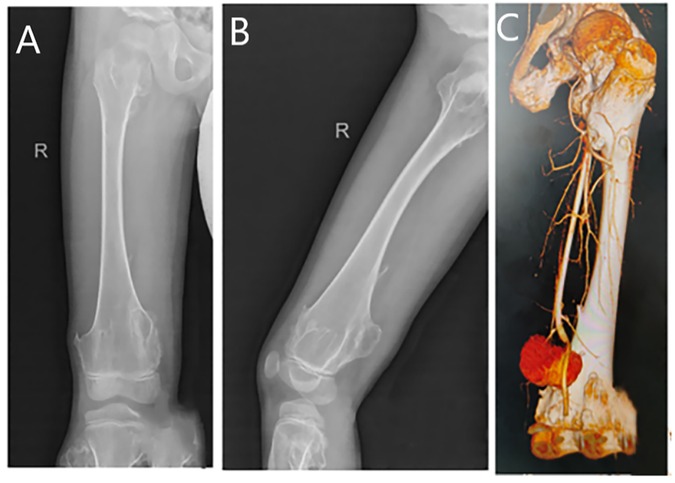

A— radiograph was performed, and genetic testing was sent for analysis. The radiograph showed an osteochondroma of the right distal femur (Figures 1A,B). Whole-exome sequencing analysis revealed a pathogenic heterozygous variant in the EXT1 gene (NM_000127.3:c.1722+1G>A) in intron 8. Sanger sequencing confirmed paternal inheritance of this variant, while the patient’s sister and mother carried the wild-type allele.

Figure 1. (A) A plain radiograph in the anterior–posterior view reveals an osteochondroma of the right distal femur. (B) A lateral view of the same plain radiograph reveals an osteochondroma of the right distal femur. (C) Computed tomography angiography shows a distal rupture of the right femoral artery with pseudoaneurysm formation.

We excised the mass from the back of the patient’s right thigh, and postoperative pathology confirmed that it was an osteochondroma. On the 10th postoperative day, the patient experienced a partial dehiscence of the surgical incision, accompanied by bleeding. The initial discharge was dark red in color, which subsequently transitioned to bright red and ultimately evolved into hematoma formation. Laboratory tests revealed a red blood cell count of 3.46 × 1012/L, a hemoglobin level of 102 g/L, and a hematocrit of 30.4%, all of which were below the normal reference ranges. An ultrasound examination revealed a cystic mass measuring approximately 14.9 cm × 6.8 cm × 4.3 cm located within the subcutaneous muscular layer. Internal blood flow signals were detected within the mass via Doppler imaging. The deep aspect of the lesion was adjacent to the right femoral artery, with an echogenic finding consistent with a fistulous tract approximately 0.18 cm in width. These findings were suggestive of a pseudoaneurysm arising from the right femoral artery, accompanied by surrounding intramuscular hematoma formation. Further computed tomography angiography revealed a sharp and rough local cortical bone at the distal end of the right femur. An irregular mass shadow was seen on the dorsal side of the lower segment of the right thigh, with a relatively thick cyst wall. Enhanced scanning revealed that the contrast agent was filling the inside of the cyst. This indicated a rupture at the distal end of the right artery and the formation of a pseudoaneurysm (Figure 1C).